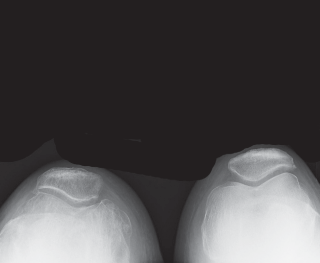

الأشعة السينية (X-rays):

تُعد الأشعة السينية هي الأداة الرئيسية لتشخيص التهاب المفاصل في الركبة. يمكنها إظهار مدى تآكل الغضروف (يظهر كضيق في المسافة بين العظام)، وتغيرات العظام، وتكون النتوءات العظمية (Osteophytes). تشمل الصور الروتينية:

- الأشعة الأمامية الخلفية (Anteroposterior - AP): تُظهر الركبة من الأمام.

- الأشعة الجانبية (Lateral): تُظهر الركبة من الجانب.

- الأشعة المحورية للرضفة (Merchant's or Sunrise View): تُظهر الرضفة وحجرتها الفخذية.